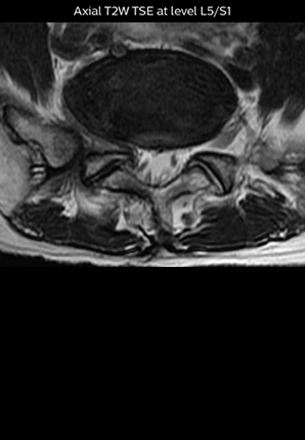

“The intra-luminal signal of veins, especially around the intervertebral space, can be suppressed well with NerveVIEW. As a result, we can easily observe the detailed nerve structure around the posterior ganglion,” he says. “This is why we use 3D NerveVIEW for intraforaminal stenosis and extraforaminal stenosis/herniation (lateral disc herniation). On the other hand, if herniation is suspected to exist inside the dorsal root ganglion (DRG), balanced TFE or ProSet-FFE is applied. NerveVIEW is not suitable for evaluating the median type of herniation.” The SE-EPI DWI-based method for MR neurography works well for large FOV exams like whole-body MRI, but focal examination of nerves is often limited by the attainable spatial resolution (both inplane and slice direction) and geometric distortion. “3D NerveVIEW achieves higher in-plane resolution – close to our other routine spine sequences – and the source images can be used instead of adding a fat-suppressed T2-weighted sequence,” Tanji says.

According to Tanji, methods such as ProSet FFE, STIR or 3D VISTA are anatomically nonselective because background signals, for instance from blood vessels, often interfere with nerves, which hampers evaluation of details, especially at the peripheral side of the nerves.

“For both brachial and lumbar plexus, we are currently using a 230 mm FOV and voxels of about 1 x 1 x 2 mm acquired (1 x 1 x 1 mm reconstructed). This provides us a good representation of the nerves, even though this FOV is relatively small. Regarding the inplane resolution, we hope to be able to bring that down to 0.7 mm, similar to our typical 2D multislice T2W images,” says Tanji.